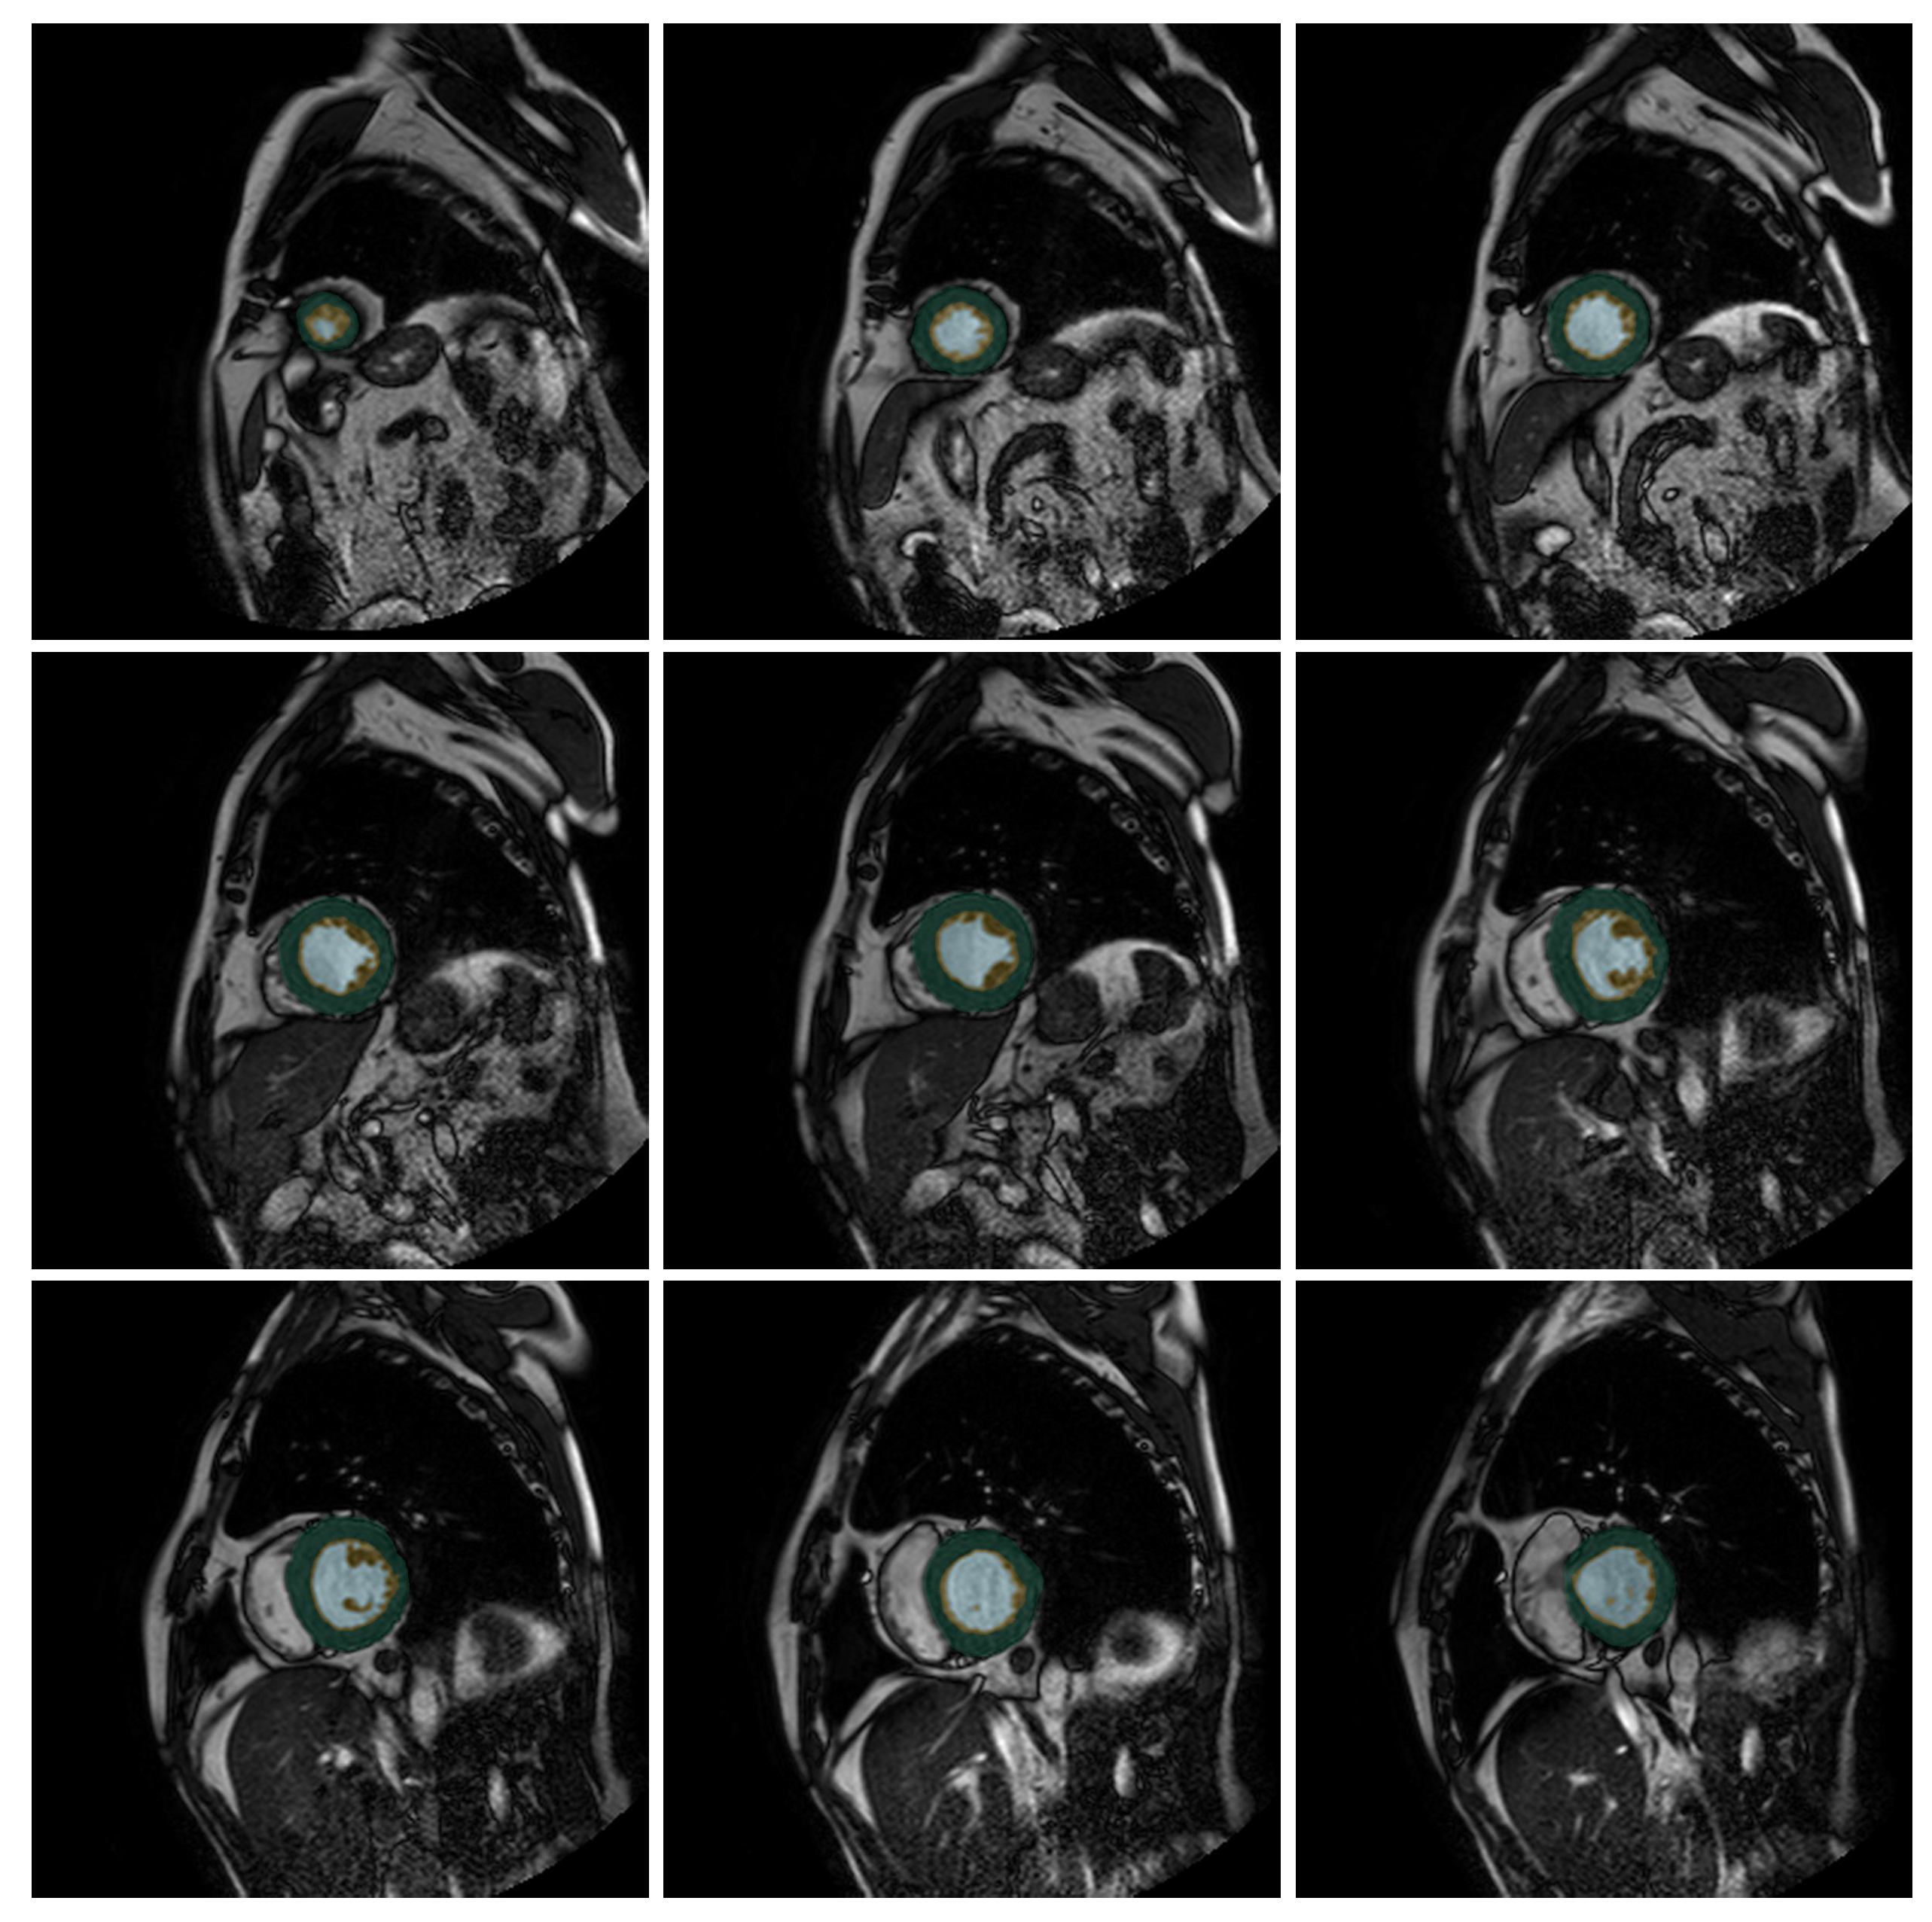

The output of our neural net looks like Figure 1, where we color three different zones: External Layer (EL), Internal Cavity (IC), and Trabecular Zone (TZ) in three different colors. Our U-Net-based proposal takes this output and calculates the VT%, giving us the access to determine if the patient has LVNC.

Figure 1.

Output slices for the patient P241 (from the test set) from the U-Net++. Green indicates the compacted external layer of the left ventricle, yellow the trabecular zone, and light blue the internal cavity.